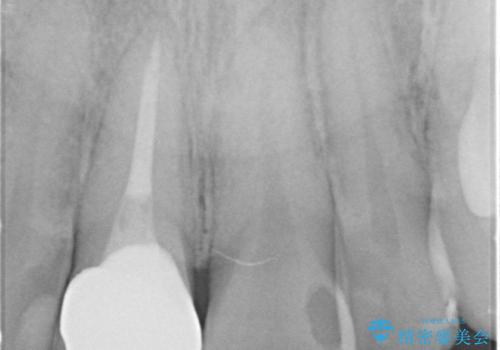

- 奥に引っ込んでいる前歯を矯正治療で並べたい!色の気になる前歯のクラウンをやり替えたい!と希望され来院されました。

奥に位置している前歯を部分ワイヤー矯正ののちマウスピース矯正インビザラインで並べ、矯正治療後に審美的なジルコニアクラウンを作製していきます。